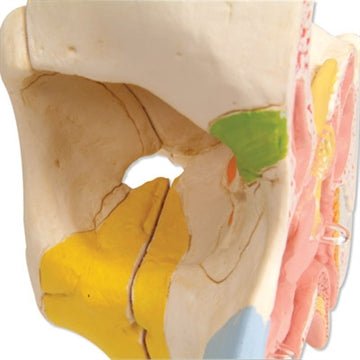

Salg af anatomiske modeller er det bærende element i eAnatomi, selvom vi også bruger mange ressourcer på at udvikle vores egne anatomiske materialer som fx plakater. Anatomiske modeller anvendes til forskellige formål og kan både vise afgrænset væv, organer samt organsystemer. Søger du en simpel model af knoglevæv eller måske en avanceret torso-model baseret på MRI teknologi, kan du finde det hele på eanatomi.com.